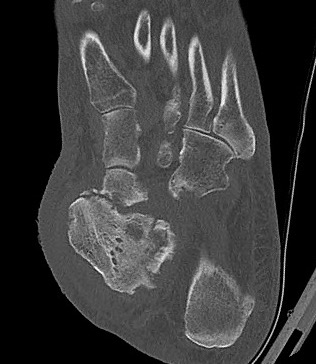

Brodsky Classification

| Type 1 Midfoot (60%) | Type 2 - Hindfoot (30%) | Type 3 (10%) |

|

Metatarsocuneiform and naviculocuneiform

Collapse of the medial longitudinal arch with rocker bottom foot |

Subtalar joint, talonavicular, calcaneocuboid

More unstable than type 1 Require longer periods immobilisation |

3a: Tibiotalar joint - most unstable pattern

3b: Fracture calcaneal tubercle - weak push-off and ulceration |